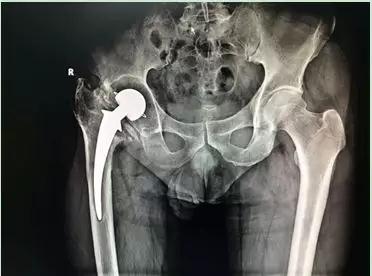

術前X線:髖關節假體已松動,假體周圍大量骨溶解

但是“松動”并不意味著假體容易取出,大多數情況下需要用各種方法用力將假體取出。同時清除初次手術中的骨水泥是髖關節翻修手術中最為費時和危險的。而由于磨損松動或者感染引起骨缺損是髖關節翻修中的最主要問題。該患者術前X線及CT檢查顯示存在大量的骨缺損,我科率先使用鈦合金骨小梁填充塊重建髖臼,完美的解決了髖臼的骨缺損問題。